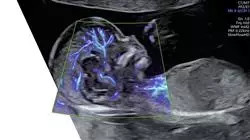

A medicina fetal é uma especialidade que fez avanços significativos nos últimos anos no diagnóstico e na prevenção do nascimento prematuro. Esse é um grande desafio para os profissionais da área médica devido à alta incidência e aos riscos associados ao nascimento prematuro, que é a principal causa de mortalidade perinatal em muitos países.

Assim, esse programa aborda de forma abrangente os principais aspectos relacionados ao diagnóstico e à prevenção do nascimento prematuro, desde a epidemiologia e o impacto da patologia, passando pelos diferentes tipos de prematuridade, até os tratamentos médicos, mecânicos e cirúrgicos disponíveis para a prevenção do nascimento prematuro. Ele também aborda tópicos específicos, como avaliação do comprimento do colo do útero, triagem precoce, ameaça de parto prematuro, administração de corticosteroides para maturação pulmonar fetal e neuroprofilaxia.

O parto prematuro é definido como aquele que ocorre antes das 37 semanas de gestação e pode ser o resultado de várias causas que afetam a saúde da mãe e/ou do feto. É uma complicação obstétrica que representa uma das principais causas de morbimortalidade perinatal em todo o mundo. Na TECH Universidade Tecnológica, desenvolvemos o Curso de Diagnóstico e Prevenção do Parto Prematuro em Medicina Fetal, com o objetivo de fornecer aos profissionais de saúde a capacitação necessária para reconhecer e tratar essa complicação em sua fase inicial. Neste plano de estudos, será aprofundado o conhecimento de diferentes técnicas de diagnóstico, como ultrassonografia e monitorização fetal, e será abordada a prevenção e o manejo de complicações obstétricas relacionadas ao parto prematuro. Os alunos poderão adquirir habilidades práticas por meio da realização de casos clínicos, a fim de melhorar seu desempenho profissional nessa área.

O Curso de Diagnóstico e Prevenção do Parto Prematuro em Medicina Fetal também foca na prevenção e tratamento de complicações perinatais associadas ao parto prematuro, como insuficiência cervical, ruptura prematura de membranas e restrição do crescimento intrauterino. Os alunos também terão a oportunidade de analisar os últimos avanços em terapia fetal, incluindo cirurgia fetal, uso de corticosteroides e tocolíticos. Resumidamente, este plano de estudos fornecerá aos profissionais de saúde uma capacitação abrangente em diagnóstico, prevenção e tratamento do parto prematuro em medicina fetal, com o objetivo de melhorar a saúde materno-fetal e reduzir a morbimortalidade neonatal.